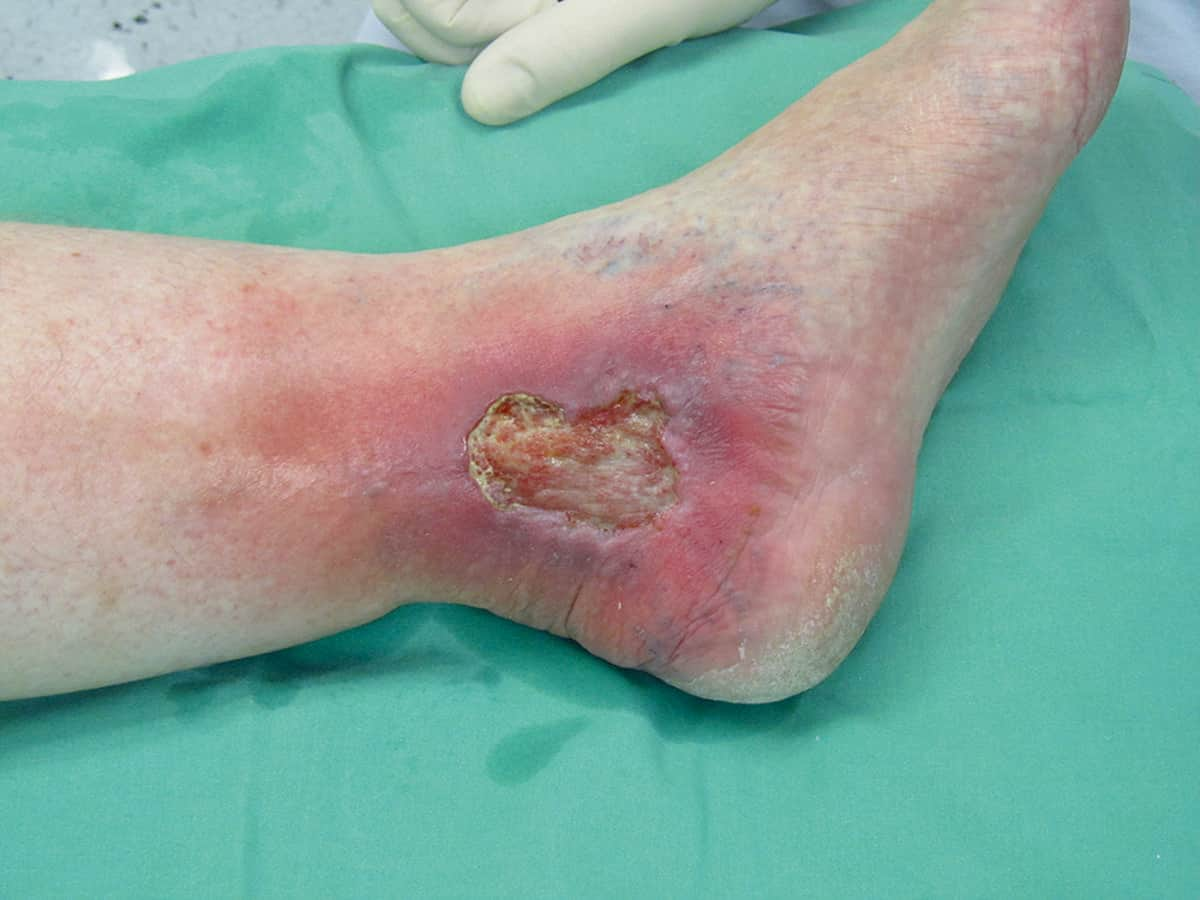

- What is a chronic leg ulcer?

- What are the different types of leg ulcers and why do they form?

- How to identify and manage a leg ulcer

Understanding venous leg ulcers and how to manage them

- What is a venous leg ulcer and why does it occur?